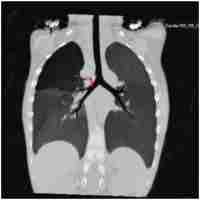

Interrupted aortic arch with a right descending aorta and right ductus arteriosus, causing severe right bronchial compression

| Abstract | SummaryWe report here a patient with interrupted aortic arch and a right descending aorta, in whom the surgical management was complicated by the development of right bronchus compression and unilateral emphysema, due to the presence of the right ductus arteriosus. |